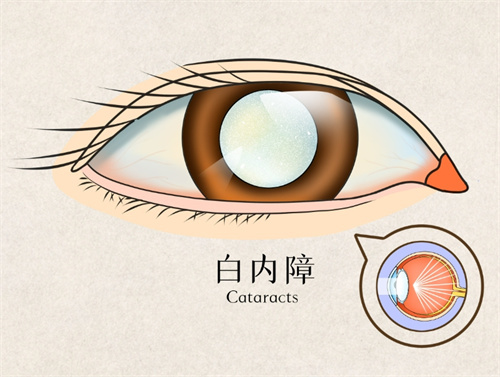

白内障超声乳化术:6800-12800元(不同晶体选择)